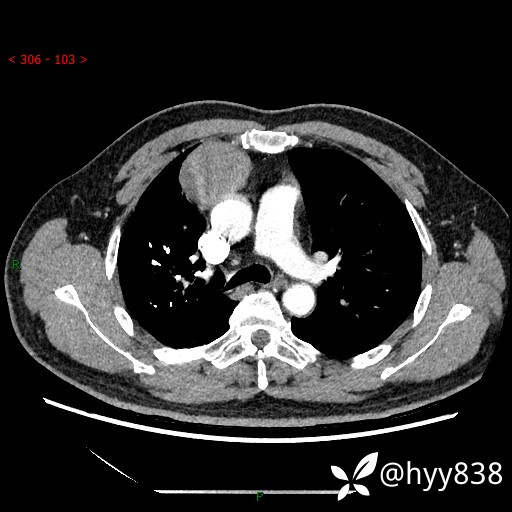

动脉期+静脉期